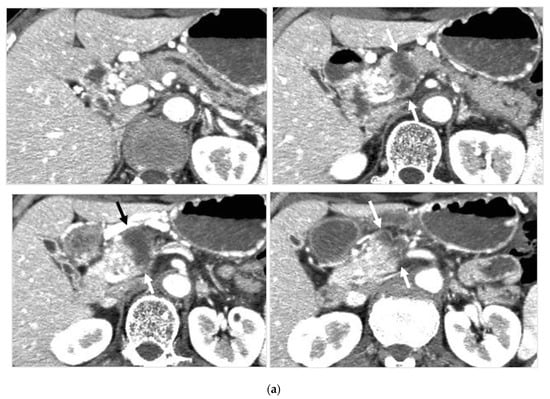

Figure 4.

Locally advanced cancer of the pancreas with excellent treatment compliance. A 78-year-old man with locally advanced pancreatic carcinoma at pancreatic body received 4 treatment courses in the first year, resulting in CR and continued life for 144 months after diagnosis. (a) Postcontrast CT (arterial phase) immediately before the first treatment course. A mass of low attenuation with maximal diameter of 3.5 cm (arrows) was observed at the proximal portion of the pancreatic body occluding splenic vein and extending to the common hepatic artery, splenic artery, and superior mesenteric artery. (b) The first arterial administration of chemotherapeutic agents (mitomycin C and epirubicin hydrochloride) mixed with contrast media after 3 weekly intravenous low-dose gemcitabine. Selective dorsal pancreatic angiography shows occlusion of the distal dorsal pancreatic artery (arrow) and severe encasement of its branches depicting a hypovascular mass (short arrows). (c) CT taken during dorsal pancreatic angiography show a dense opacification of most parts of the tumor (arrows). Note opacification of wall of common hepatic artery (short arrow). Twelve milliliters of contrast media (20 mL) mixed with chemotherapeutic agents were administrated at the dorsal pancreatic artery. Two milliliters of a mixture of contrast media and chemotherapeutic agents were also administrated at the pancreatica magna artery (not shown). (d) Postcontrast CT (arterial phase) after two treatment courses showed a marked decrease in the size of the tumor (arrow), which had no enhancement effect until the parenchymal phase. Note the atrophy of the pancreatic body and the tail and splenic vein. After this arterial administration, all elevated tumor markers became normal, including CA19-9 (142.7 U/mL → 7.9 U/mL), elastase-1 (1340 ng/dl → 121 ng/dL), and SPAN-1 (110 U/mL → 5.7 U/mL). The patient showed no sign of recurrence for 11 years.